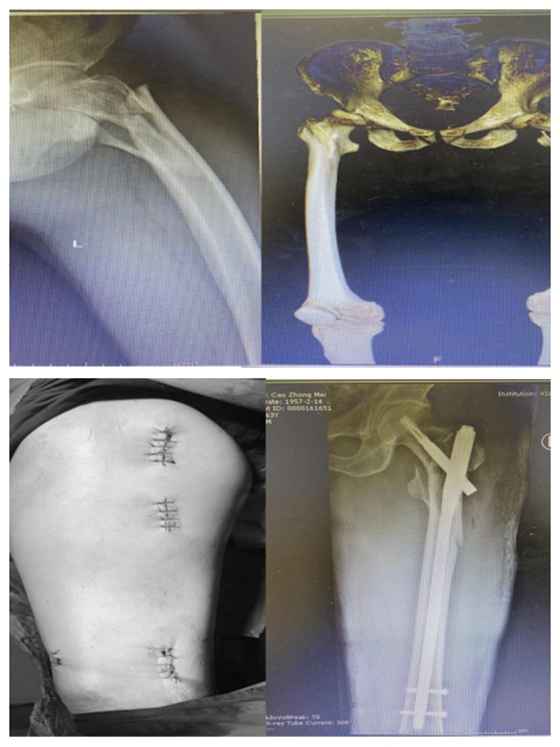

患者:曹某,78岁

湘雅常德医院开院以来,主要收治的髋部骨折患者年龄从70-102岁不等,且多伴有心肺功能不全,合并多种内科疾患,具有手术风险高、难度大的特点。在科主任张朝跃主任医师和创伤组长王穗源副主任医师的带领下,与全院各临床科室、麻醉、手术部进行多学科合作,开展了一系列针对高龄及超高龄患者的髋部骨折个性化手术治疗,术后2-3天即可扶助下地行走,患者及家属满意度极高,极大地减轻了老年患者的痛苦,延长了患者的生命,减轻了家庭护理负担,获得了良好的社会口碑。